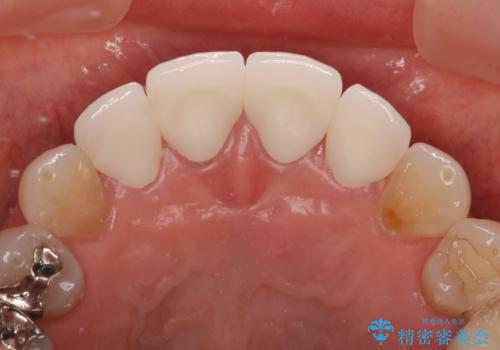

前医で仮歯を装着する前の口元の写真をいただき、咬み合わせや形態を参考にしながら仮歯で仕上がりをイメージし、最終的に満足のいくオールセラミッククラウンを装着することができました。